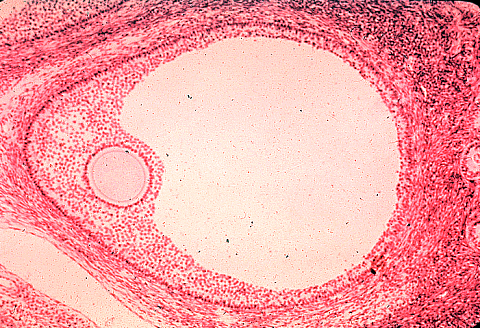

В середине XVII века появляются первые микроскопы, благодаря которым произошла настоящая революция в науке. В 1672 году нидерландский ученый Р. де Грааф опубликовал сообщение «О женских органах, служащих делу размножения», в котором он впервые описал структуру яичника. Грааф первым обнаружил в яичнике пузырек, который в дальнейшем был назван его именем — граафов пузырек (зрелый фолликул).

Грааф думал, что этот пузырек и есть «женское семя» — яйцеклетка. На самом деле, как выяснилось позднее, яйцеклетка находится внутри граафового пузырька и окружена тысячами других клеток, которые обеспечивают ее питание.